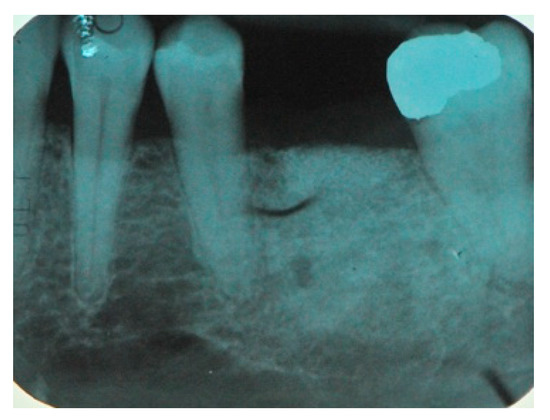

| Patient | Atrophic Site | Initial Width | Initial Height | Final Width | Final Height | Fixture |

|---|---|---|---|---|---|---|

| 1 | 36 | 4.2 ± 0.8 | 6.2 ± 0.8 | 8.9 ± 1.2 | 11.1 ± 2.2 | 1 |

| 2 | 24–25–26 | 2.9 ± 0.9 | 2.3 ± 1.3 | 6.1 ± 0.5 | 9.8 ± 0.3 | 3 |

| 3 | 12–11–21–22 | 3.8 ± 0.5 | 11.2 ± 0.5 | 6.8 ± 0.3 | 11.3 ± 0.5 | 4 |

| 4 | 36 | 3.1 ± 0.2 | 8.3 ± 0.8 | 7.2 ± 0.9 | 11.5 ± 0.3 | 1 |

| 5 | 14–15–16 | 3.1 ± 0.5 | 4.2 ± 0.2 | 6.4 ± 0.5 | 9.5 ± 0.5 | 3 |